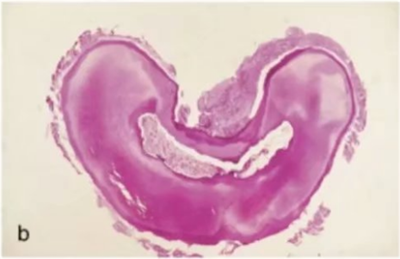

在一項(xiàng)包含了 149例下頜第二磨牙的研究中,Manning 發(fā)現(xiàn) 76%的下頜第二磨牙為雙根,22%為單根,2%為三根。在另一項(xiàng) Vertucci 報(bào)道的包含了 100 例下頜第二磨牙的研究中,近中根中,單根管為 27%,雙根管融合為單根管為 38%,兩個(gè)獨(dú)立的根管為 35%。遠(yuǎn)中根中,Vertucci發(fā)現(xiàn) 92%為單根管,兩根管融合為單根管為 3%,兩個(gè)獨(dú)立的根管為 5%)。Beatty 和 Krell 報(bào)道了一例下頜第二磨牙遠(yuǎn)中根三根管的病例。下頜第二磨牙單根與雙根的根管結(jié)構(gòu)可能相同,或也都可能為 C 型根管系統(tǒng),其以獨(dú)立的根管間存在弧形或網(wǎng)狀峽區(qū)為特征。C 型牙根和根管系統(tǒng)的形成可能與牙根頰側(cè)或舌側(cè)表面的 Hertwig 上皮根未融合或不完全融合相關(guān)。白種人中 C 型根管的發(fā)生率在2.7%~7.6%;

但是,在其他的種族中,C 型根管的發(fā)生率可能會(huì)明顯的升高,如在中國(guó)人中,發(fā)生率可能高至 31.5%。C 型根管也可能存在多種變異形態(tài)。Fan 等人,使用顯微 CT 檢查了 58 例下頜第二磨牙的 C 型根管結(jié)構(gòu),掃描范圍從髓室至根尖,間隔0.5mm。

根據(jù)不同層面根管截面的形狀,C 型根管被分為如下 5 類:

C1:根管橫截面形態(tài)為連續(xù)不間斷的 C 型;

C2:C 型根管輪廓中斷呈分號(hào)狀;

C3:根管數(shù)目為 2 或 3 個(gè),其中存在峽部連接;

C4:根管截面為圓形或橢圓形;

C5:截面未觀察到管腔形態(tài)。

大部分 C 型根管系統(tǒng)在根管口處為連續(xù)的 C 型結(jié)構(gòu);但是,沿著牙齒牙根方向,橫截面形狀可能是 C1,C2 或 C3 的任一種。C4 和 C5 幾乎只能在根尖附近的橫截面見到(圖 15a-c)。C 型根管的下頜磨牙在清理、預(yù)備成型及充填方面都存在挑戰(zhàn),特別是,當(dāng)髓室底發(fā)現(xiàn)C 型根管口時(shí),不能確定根管在到達(dá)牙根根尖 1/3 時(shí)是否是連續(xù)的。在定位 C 型根管系統(tǒng)主根管分叉為兩根管或三根管的部位及識(shí)別根管間的峽部時(shí),手術(shù)顯微鏡是很有幫助的(圖16a-b)。C 型根管沖洗時(shí)應(yīng)盡量使用超聲銼活化沖洗液。